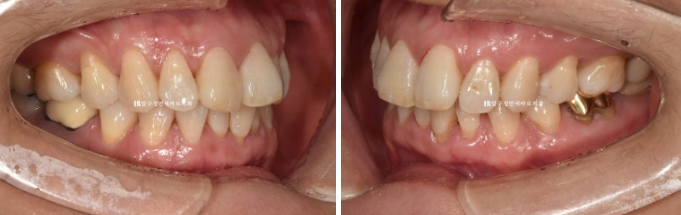

50대 환자분께서 앞니가 점점 뻗치고 틀어져서 교정을 위해 내원하셨습니다.

오래 전 발치교정이 이미 끝났는데 나이가 들면서 점점 앞니가 틀어져서 앞니 부분교정을 위해 오셨습니다.

위 앞니 두개가 튀어나와있고 회전이 되어있습니다.

정식용어는 아니지만 이런 치아를 나비치아 라고 합니다.

이 정도면 인비절라인 라이트로 충분한 교정이 가능합니다.